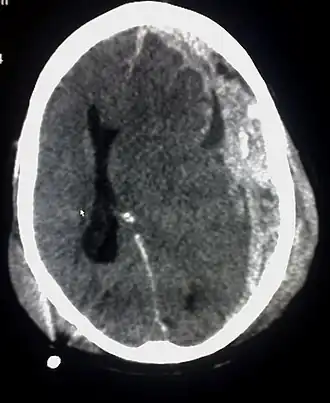

Se acepta que HIC (CLE) es sólo un predictor correlacionado positivamente con la probabilidad de daño, y que no existe una conexión determinista entre el valor de HIC de un impacto y los daños, ya que el mecanismo de lesión es complejo y depende tanto de la dirección exacta de la aceleración, como de la región cerebral que más aplastamiento sufra contra el interior del cráneo. Diversos estudios de casos prácticos han encontrado mediante correlación logística que existe una relación de tipo logístico entre la probabilidad de daños severos y el valor de HIC en un evento de desaceleración severa como el experimentado por el ocupante de un vehículo que impacta frontalmente contra otro. Más concretamente la relación es del tipo:[4]